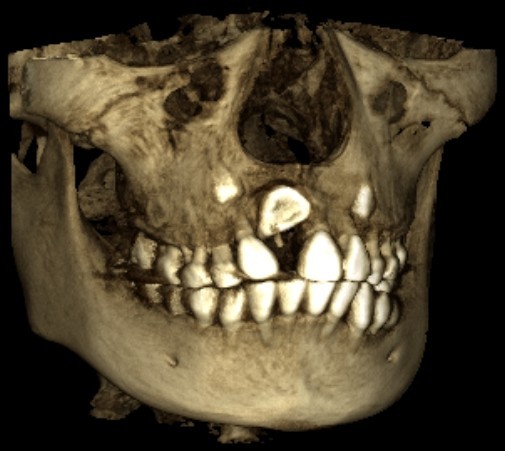

颅颌面CBCT

诊断范围涉及牙体牙髓病、牙周病、阻生牙/多生牙定位、种植牙术前CT评估分析、颞下颌关节CT诊断分析、,颌骨及涎腺疾病、颌面发育畸形、正畸治疗辅助诊断等大部分颌面部疾病,为临床医疗提供强有力的支持。